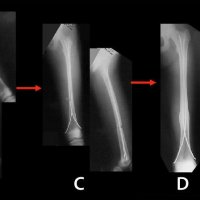

TITANIUM ELASTIC NAILING (TEN)

Titanium Elastic Nailing (TEN) is intended for fixation of diaphyseal fractures of long bones where the medullary canal is narrow or flexibility of the implant is paramount. The biomechanical principal of the Titanium elastic nailing is based on the symmetrical bracing action of two elastic nails inserted into the metaphysis, each of which bears against the inner bone at three points. The complication rates associated with Titanium elastic nailing have been reported to be minimal.